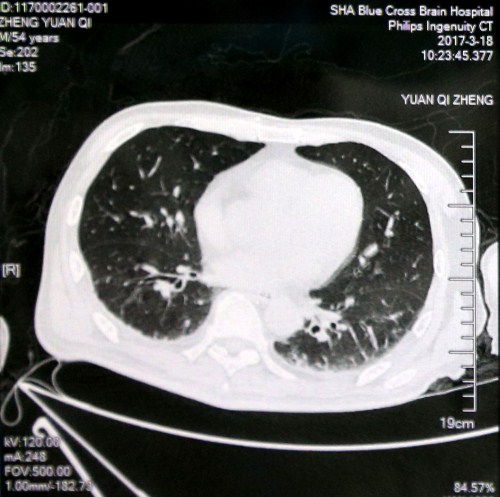

入院初肺部CT影像:双肺炎症

最近肺部CT影像:双肺炎症较前减少